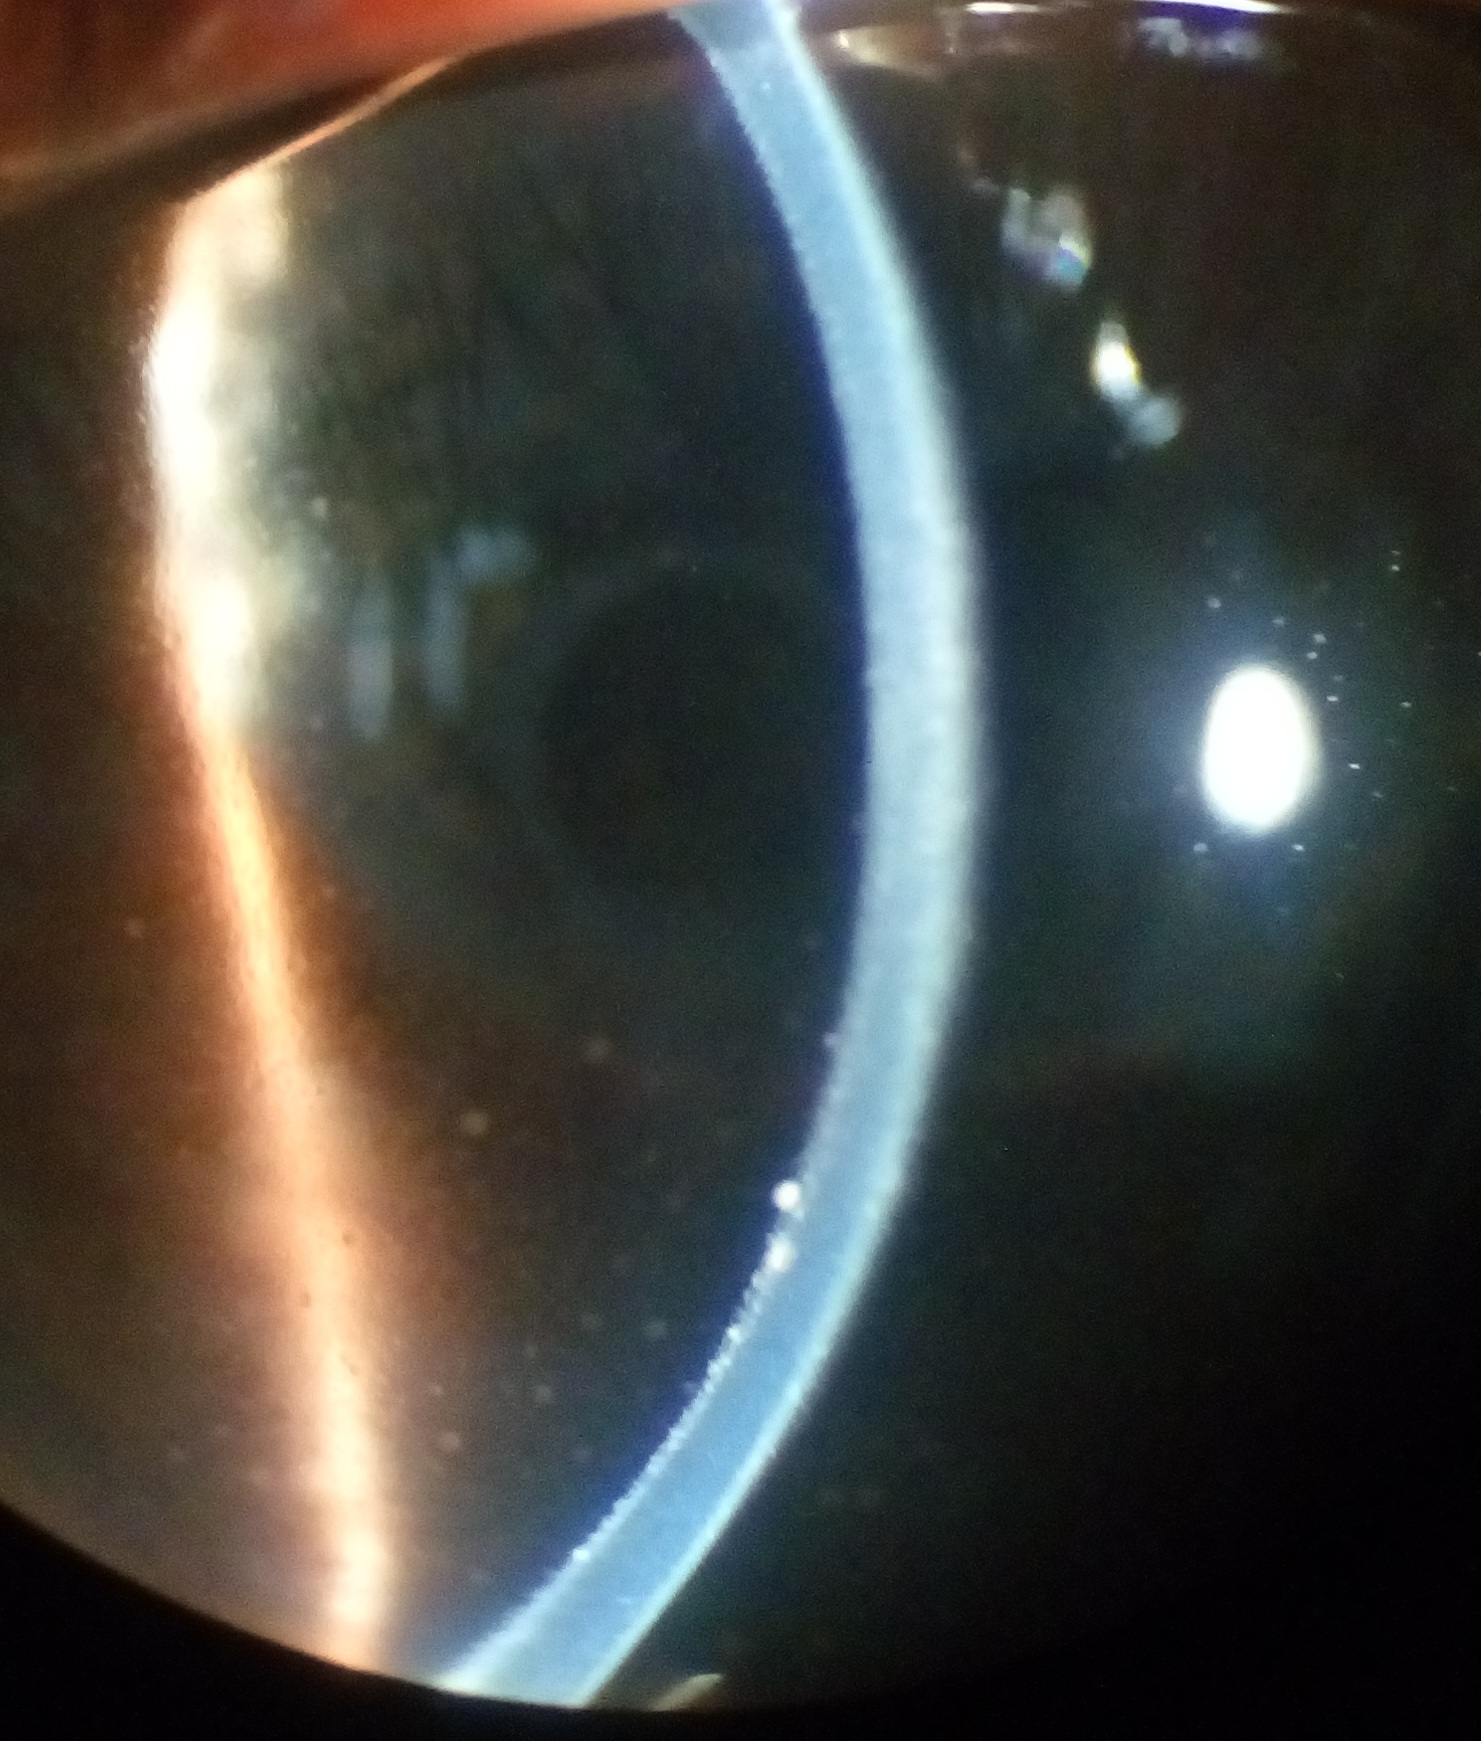

Keratic precipitate due to Vogt-Koyanagi-Harada Disease. Note granulomatous deposits on corneal endothelium.

| current | 02:47, June 2, 2017 | 1,481 × 1,741 (723 KB) | Kabir.Hossain (talk | contribs) | Keratic precipitate due to Vogt-Koyanagi-Harada Disease. Note granulomatous deposits on corneal endothelium. |